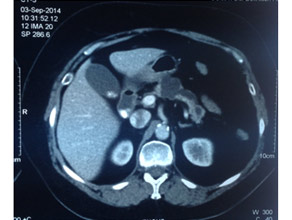

CT of pancreatic head mass showing stipled calcification

CT scan of pancreatic head mass